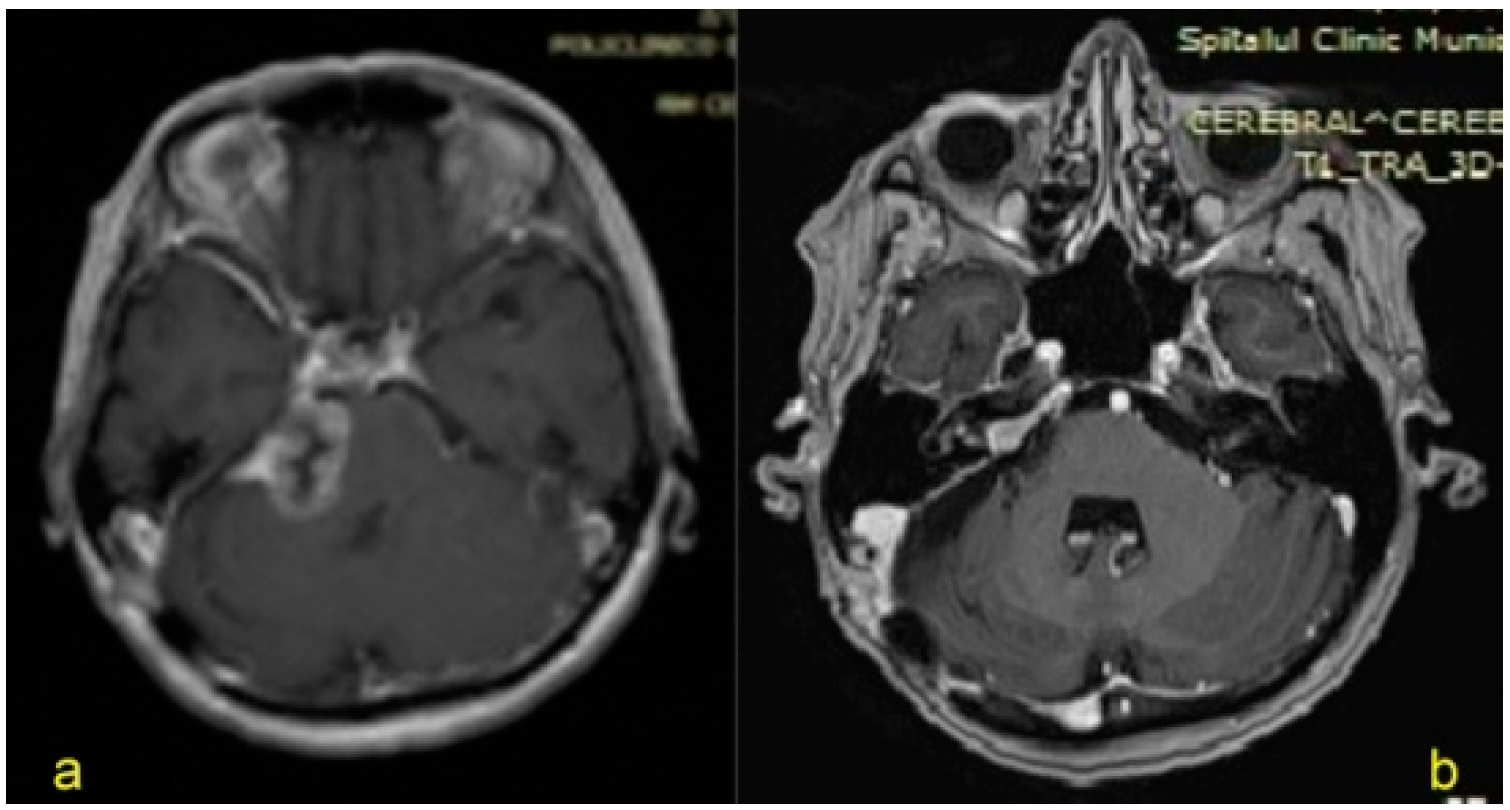

| 3. | 64/M | VS (Apr 2015) Koos grade IV | - | 26 | Tarsorrhaphy | VI/IV (left side) Total paralysis/Disfiguring weakness, incomplete eye closure and asymmetric at rest | CSF leak Hydrocephalus (VCS, right VP shunt) |